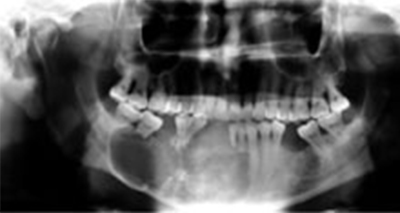

There a lot of tumors that varies from less than 1 cm in diameter and length to very extensive in size that requires more than hemimandibulectomy which means resection of more than half of the jaw, depending on the size and aggressiveness of the tumor lesion.

In case of extensive resection reconstruction of the defect is mandatory to the patient to restore both functions and esthetics.